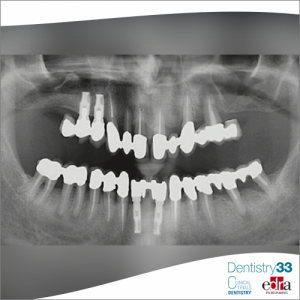

Oral pathology 01 December 2021

Authors: Giulia Pradal, Daniela Sorrentino, Niccolò Lombardi, Alberto Pispero, Laura Moneghini

A 76-year-old male patient was sent to the oral medicine service of the San Paolo Hospital in Milan for the presence of a radiolucent lesion at the level of the left mandibular corner, found through...